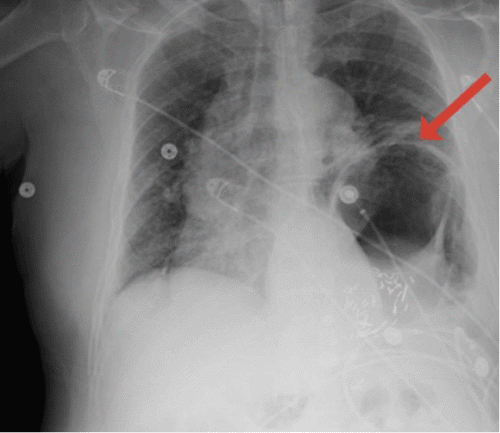

On physical examination, his abdomen was soft, non-distended, and had generalized tenderness with no guarding or rigidity. A bedside ultrasound of the abdomen did not show significant findings. Chest X ray revealed significant elevation of the left hemidiaphragm with a prominent distended gastric bubble within the left thoracic cavity (Figure 1). An abdominopelvic CT demonstrated a type IV traumatic diaphragmatic hernia on the left, which contains the splenic flexure of the colon and most of the stomach (Figure 2).

Figure 1. Chest X Ray Showing Left Diaphragmatic Hernia with Distended Gastric Bubble within Left Thoracic Cavity. Published with Permission